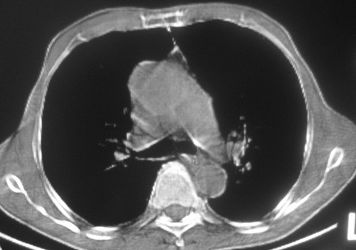

以下是引用卜一在2007-10-7 9:38:00的发言:[br]左下肺胸膜下团片影,内见含气支气管像,临近胸膜未见增厚。多考虑:1 左下肺炎症,建议消炎后复查!2 不除外肺隔离症合并感染!